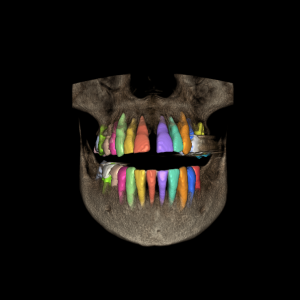

Diseño y colocación de implantes

Diseño y colocación de implantes / Fabricación de guía quirúrgica

Técnica Doble Dicom / Técnica Dicom Stl

Planificación Implantes en base al encerado

Planificación implantes

Técnica Doble Dicom

Técnica Dicom Stl